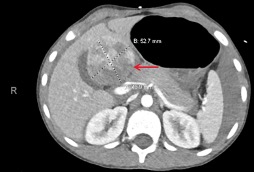

A 22-year-old man with morbid obesity presented to the clinic with a painless lump in his upper abdominal wall that had grown by 30% to 40% from October 2019 to January 2020.

02/16/2023